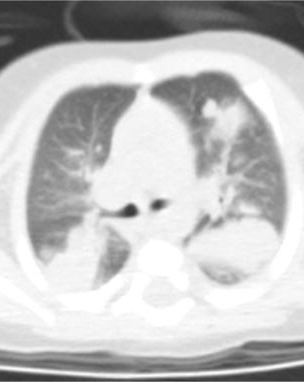

6.機(jī)會(huì)感染(如肺囊蟲病、肺曲霉菌病等)